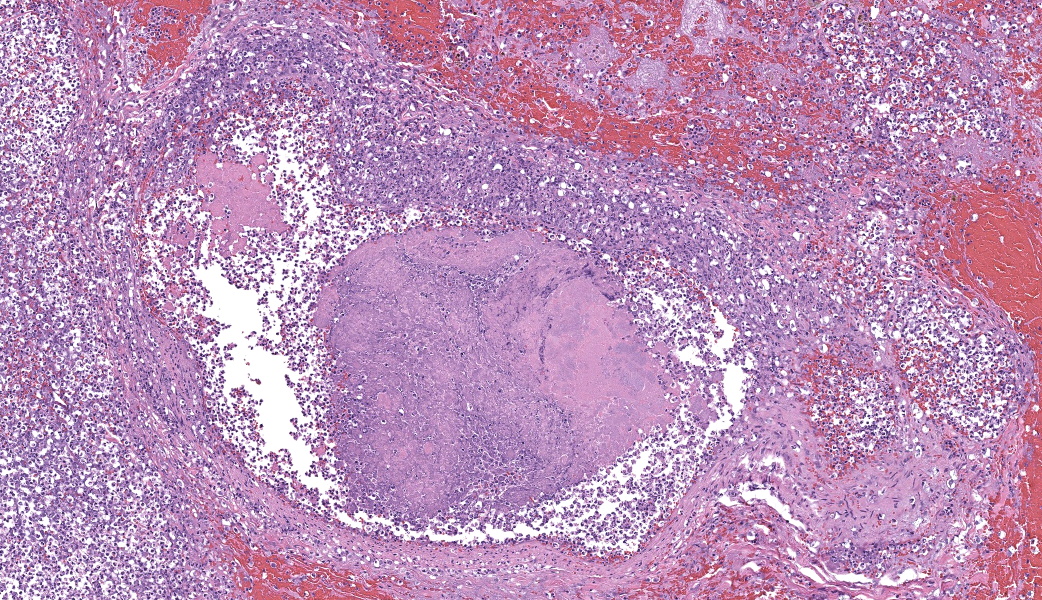

Regionally, sharply demarcated areas of the pulmonary parenchyma are markedly necrotic and replaced by abundant hemorrhage, fibrin, inflammatory infiltrates composed mainly of neutrophils and macrophages, and necrotic cellular debris. In these areas, multiple blood vessels contain thrombi consisting of large numbers of degenerate neutrophils, organizing fibrin, occasional colonies of bacterial coccobacilli, and necrotic cellular debris that variably obscure the lumen and vessel walls. Affected vessels often have smudgy, hypereosinophilic walls that are transmurally infiltrated by neutrophils, lymphocytes, and macrophages. In less affected regions, the alveolar spaces contain a small amount of fibrin, numerous foamy alveolar macrophages (some of which contain brown granular hemosiderin pigment), and fewer neutrophils and erythrocytes. There are moderate numbers of hemosiderin-laden macrophages mostly concentrated around pulmonary arteries, multifocally. Regionally, along the pleural surface there is a large amount of fibrin admixed with numerous degenerate neutrophils and necrotic cellular debris. The pleura itself is mildly thickened by fibrous connective tissue and edema and is multifocally lined by markedly reactive mesothelium, characterized by plump, rounded mesothelial cells.

As the adherence of bacteria and blood components to the valve leaflets progresses, irregular, raised vegetations replace the smooth valvular surface.5 Portions of such vegetations may become detached and travel throughout the body as septic emboli.5 Emboli arising from the right side mainly affects the lungs, while emboli from the left side may dislocate and travel to distant organs, such as kidney and spleen.5

In the current case, right-sided valvular endocarditis was observed, most likely a consequence of a contaminated venous injection. Septic emboli translocated to the lungs, causing pulmonary thrombosis and infarction. Bacterial cultures of the heart and lungs revealed large numbers of E. coli and fewer Staphylococcus sp.

2. Lung: Pneumonia, embolic, necrotizing and suppurative, chronic, multifocal to coalescing, severe, with septic arterial thrombi and suppurative pleuritis.